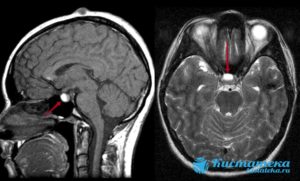

Если предполагается злокачественный характер опухоли, показана консультация онколога. Один из самых информативных методов диагностики – МРТ исследование, которое позволяет дифференцировать кисту, сформировавшуюся в зоне кармана Ратке, от таких патологий, как арахноидальные кисты или аденомы гипофиза (пролактиномы).

На снимке отчетливо видно хорошо отграниченное новообразование кистозной структуры округлой или продолговатой формы иногда с утолщенной стенкой. КТ-томография показывает большую плотность ткани кисты по сравнению с окружающей мозговой тканью.

Магнитно-резонансная томография

Кисты кармана Ратке почти всегда имеют гомогенную интенсивность МР сигнала, в то время как кистозные краниофарингеомы и аденомы с кровоизлиянием имеют гетерогенный сигнал. [9] Уровни жидкости подразумевают кровоизиляние в анамнезе. Хотя кисты кармана Ратке не имеют характерных только для данной нозологии МР признаков. Большинство кист можно отнести к двум группам:

- Кисты кармана Ратке с низкой интенсивностью МР сигнала на Т1 взвешенных изображениях и высокой интенсивностью сигнала на Т2 взвешенных изображениях,

- Кисты кармана Ратке с высокой интенсивностью МР сигнала на Т1 взвешенных изображениях и различной интенсивностью МР сигнала на Т2 взвешенных изображениях

В первой группе содержимое кисты серозное и имеет сигнальные характеристики соответствующие ЦСЖ. Во второй группе содержимое кист богато мукополисахаридами, которые считаются продуктами муцин-продуцирующих клеток в стенке кисты.

В редких случаях повышенный сигнал на Т1 взвешенных изображениях сочетается с низким МР сигналом на Т2 взвешенных изображениях за счет комбинации факторов включающих наличие мукополисахаридов, продуктов распада гемоглобина, высокого содержания холестерола и сушенных клеточных масс.

Сигнальные характеристики в соответствии с содержимым кисты:

- T1

- 50% гиперинтенсивные (высокое содержание мукополисахаридов)

- 50% гипоинтенсивные

- T2

- 70% гиперинтенсивные

- 30% изо- и гипоинтенсивные

- T1 C+

- отсутствие контрастного усиления

- может присутствовать тонкое кольцевидное усиление прилежащей ткани гипофиза за счет сдавления [3,4]

- может присутствовать тонкое кольцевидное усиление отражающее метаплазию эпителия

Главным методом для обнаружения кисты является магнитно-резонансная или компьютерная томография. Так как это образование похоже на аденому гипофиза и краниофарингиому, то чаще всего необходимо дополнительное введение контрастного вещества. К наиболее важным диагностическим критериям кисты кармана Ратке относятся:

- расположение внутри турецкого седла, или она выходит и за его границы;

- форма – овал, гантель, круг;

- находится между передней и средней долей;

- размер обычно 1-2 см, реже бывают крупные – до 4-5 см, они могут разрушать костные ткани;

- при введении контраста не накапливает его;

- границы четкие;

- однородной структуры;

- не содержит отложений кальция в отличие от опухолей.

На снимке МРТ стрелочками указана киста и аденогипофиз, который всегда деформирован кистой, и киста непосредственно к нему прилегает

Плотность содержимого кисты ниже, чем окружающая ткань, если преобладает жидкостный компонент внутри. При усиленном накоплении белков и мукополисахаридов консистенция становится желеобразной. В редких случаях имеется неоднородность сигнала за счет того, что присутствуют включения жиров, распавшейся крови, слущенного слоя эпителия, который выстилает изнутри кисту.

Окружающая ткань гипофиза может выглядеть более плотной, так как отмечается сдавление его клеток. При аденоме, наоборот, соседние области разрежены, так как максимальная гормональная активность наблюдается внутри опухоли.